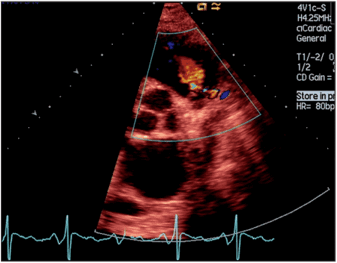

По данным ЭКГ были выявлены изменения, подтверждающие нарушение функции правого желудочка, обусловленные данной регургитацией. Электрический импульс по нему проходил более длительное время вследствие его гипертрофии и увеличения объёма, что выражалось в удлинении комплекса QRS до 125 мс (норма до 80 мс; риск внезапной смерти >180мс). При выполнении эхокардиографии наличие регургитации на клапане лёгочной артерии было подтверждено. Обратный поток крови из легочных артерий в момент расслабления правого желудочка имел умеренную вторую степень (Рис. 1 и 2).

Рис. 2 — ЭхоКГ до операции

ЭхоКГ при ЛР. ЛР диагностируют с помощью ЭхоКГ (рис. 36). Оценка степени тяжести проводится так же, как при АР.

Рис. 36. ЛР, ЭхоКГ: одновременная регистрация В-ре- жима и ЦДК, парастерналь- ная позиция по короткой оси ЛЖ. Поток ЛР в диастолу визуализируется красным цветом.